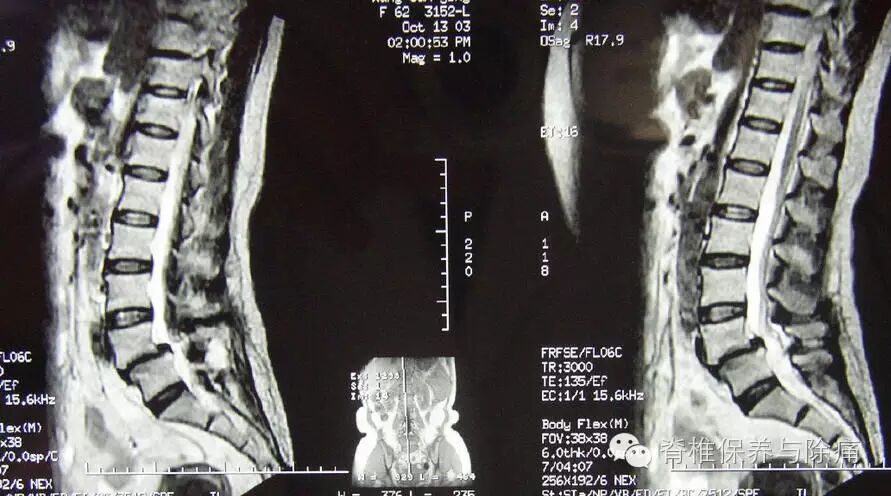

2.体征 侧隐窝型腰椎管狭窄症嵌压神经根严重的病例可出现下肢感觉障碍、肌肉力减弱、腱放射减弱或消失,直腿抬高试验阳性等与腰椎间盘突出症相似的临床特征,并难以区别。3.影像学检查(1) X线平片:可发现侧隐窝型腰椎管狭窄者的关节突肥大增生并向外膨出呈球形关节,上关节突上升,下关节突有反应性密度增高。有时可见上关节突移位,增生的骨质伸人椎间孔。(2) CT检查:可清楚地显示椎管横断面的骨性结构,对侧隐窝狭窄、椎间小关节病变有着更准确的鉴别诊断意义。是侧隐窝型腰椎管狭窄与后侧型腰椎间盘突出症鉴别诊断不可缺少的手段。(3) MRI检查:对腰椎管狭窄的诊断价值比CT及椎管造影大,也比椎管造影CT扫描(CTM)优。在T2加权图像上,可以直接观察到椎体的骨赘突向侧隐窝、骨化的后纵韧带增厚,及向侧隐窝的延伸所导致的椎管狭窄和对神经根的压迫。